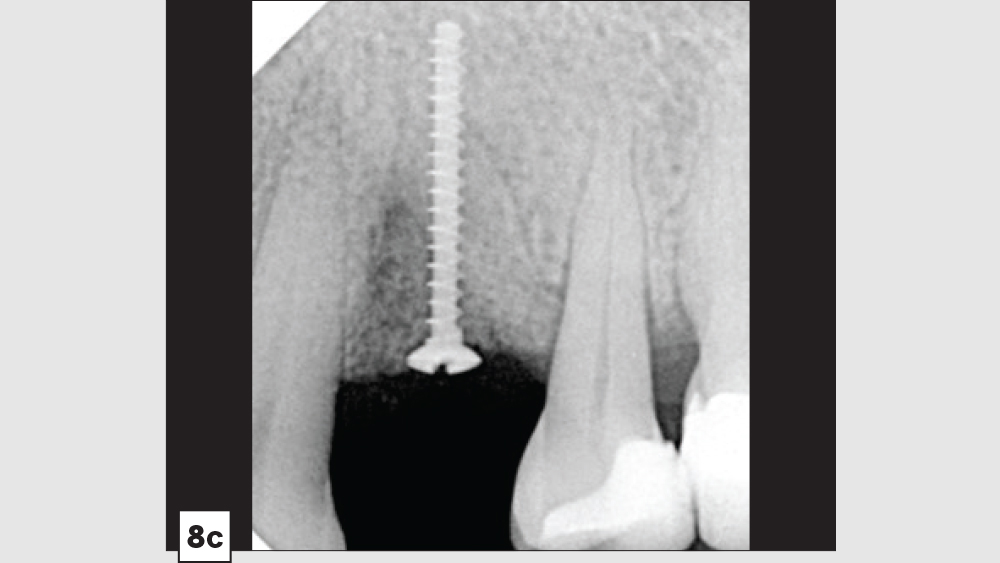

Three-Walled Socket Bone Grafting Technique (Figs. 8a–8d)

Figure 8c

Figure 8d

Figures 8a–8d: Three-walled socket: failing tooth with bone loss (8a), example of three-walled socket (buccal and lingual walls missing) (8b), graft with tent screw (8c), post-op healing (8d).

2. Preparation: After soft-tissue removal, it is imperative to decorticate the remaining walls of bone. The induced trauma from decortication will initiate the regional acceleratory phenomenon (RAP), which will facilitate early vascularization and initiate the healing process. In most three-walled sockets, tent screws are used to maintain space and increase predictability in the larger defect sites.

3. Grafting Material: The autogenous harvested bone should be placed on the host bone defect as the first layer. Particulate allograft is ideally used to fill in any voids and to maintain space. Because autogenous bone is fast-resorbing, the combination of autogenous bone and allograft is beneficial to maintain space and allow sufficient time for bone growth.

4. Membrane: In most three-walled sockets, a long-acting membrane (e.g., a collagen cross-linked membrane [Newport Biologics Resorbable Collagen Membrane 4-6] or a PTFE [CytoSurg Non-Resorbable PTFE Membrane]) is recommended. The barrier membrane is modified to encompass the missing socket walls. With these large defects, membrane tacks may be used to prevent any micromovement of the membrane.

5. Closure: Closure should be completed with a 3-0 or 4-0 high-tensile suture material (e.g., PGA or PTFE). Care should be exercised to avoid suturing through the membrane.